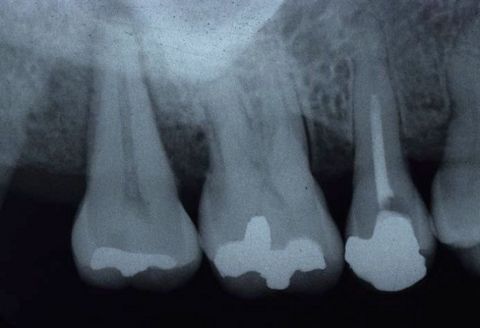

Initial situation: A healthy 34-year-old female patient with no periodontal diseases, presented at the dental clinic with the chief complaint of aesthetic problems due to the exposure during smiling of a root affected by gingival recession.

Treatment: The treatment included a coronally advanced flap (CAF) because there was an amount, even if very small of remaining keratinized tissue (1 mm). The patient’s biotype was thin, and the affected root was buccally displaced. The rationale of using Emdogain® was to improve the quality of the attachment between the newly formed connective tissue and the root surface. By depositing the Amelogenins on the root, Emdogain® promotes the cells of the blood clot to be transformed in cementoblasts and fibroblasts, and this eventually improves the quality of new connective tissue attachment with respect to long junctional epithelium. Another reason why Emdogain® was used, was to improve the soft tissue healing and this is important when the patient has aesthetic requests, as the patient do not want to wait only for the long-term outcomes but short-term results as well. Furthermore, it was decided to add the use of mucoderm® because the objective was not to only achieve root coverage which can be achieved with CAF itself, but also to increase the soft tissue thickness, which is a condition that is a critical for the long-term maintenance of the outcome. In terms of post-operative course, it was optimal. The patient did not have any pain at all, she presented no swelling nor hematoma, and from the first follow-up visit there was a nice adaptation and blending of the treated area.